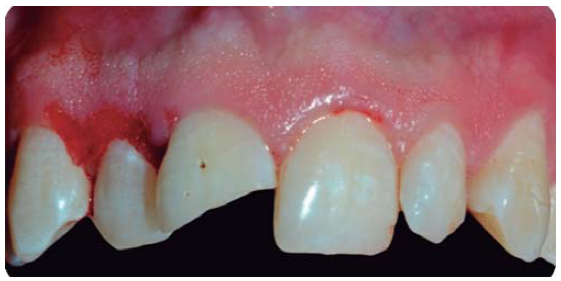

Debido a la evolución de dos días desde el accidente, el paciente presenta dolor e inflamación a la exploración extraoral, durante la exploración intraoral se observa la exposición pulpar de los dientes involucrados (Figura 2) e indica el tratamiento de urgencia a seguir, para disminuir el dolor e inflamación.

Paciente de sonrisa gingival que presenta fractura complicada de corona del diente 21 en el tercio medio coronal (Figura 3) y del diente 12 en el tercio cervical (Figura 4), fractura complicada de corona y raíz del diente 11 (Figura 5); gingivitis inducida por placa dentobacteriana (Figura 7), trasposición de los dientes 13 y 14, anodoncia verdadera de los dientes 15, 35 y 45, presentando los dientes temporales 55, 75 y 85.

Alargamientos de coronas con fines endodónticos y restaurativos

Con una hoja de bisturí 15c, se realiza una incisión a bisel interno y luego una intrasurcal para eliminar un collar de encía y continuar levantando un colgajo de espesor total para exponer la estructura radicular remanente (Figura 8).

Se realizan las medidas con una sonda periodontal, para determinar la cantidad de tejido óseo que se debe eliminar con la osteotomía y osteoplastia para asegurar el efecto férula necesario para las restauraciones provisionales. Se mide con la sonda para asegurar una osteotomía de mínimo 3 mm (Figura 9), se procede a suturar con puntos simples (Figura 10).14

En la historia clínica, el paciente reveló que sus dientes incisivos centrales superiores presentaban diastemas, por lo cual durante la misma cirugía se procede a liberar el frenillo labial superior por medio de una frenilectomía, ya que su inserción era baja (Figura 10).15